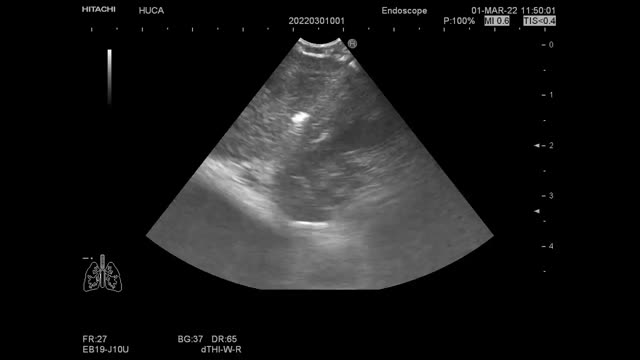

All four patients underwent EBUS-TBNA (EB-1970UK, Linear-Array; Pentax Medical, Tokyo, Japan) under conscious sedation with midazolam and fentanyl after signing informed consent. The procedure was performed by an interventional pulmonologist with multi-year experience in performing EBUS-TBNA. The clinical characteristics of the patients and the findings at bronchoscopy with both EBUS-TBNA and TMC are shown in Table 1. Rapid onsite evaluation (ROSE) was done on the EBUS-TBNA sample, and cell blocks were prepared from the obtained material. We proceed to describe step by step the complete procedure applying the Ariza-Pallarés method using case 4 of Table 1 as the main example. A 53-year-old male was referred to our Interventional Pulmonology Unit (IPU) in January 2022 to perform a mediastinal biopsy due to suspicion of relapse of B-cell non-Hodgkin lymphoma previously diagnosed in 2016. EBUS-TBNA of station 7 was made at that time without being conclusive; therefore, a mediastinoscopy was performed reaching the final diagnosis. We decided to perform TMC given the relevance of the case. A fluorodeoxyglucose positron emission tomography (FDG-PET) scan showed an increased FDG uptake at 7 and 11Rs stations (Fig. 1A). After identification of an enlarged station 7 lymph node at EBUS (Fig. 1B), the pulmonologist performed four passes of TBNAs with 22-gauge needle. After initial puncture with the EBUS-TBNA needle, a 1.1mm cryo-probe (Erbecryo 20402-401, Tubingen, Germany) was introduced into the working channel of the EBUS bronchoscope. The cryo-probe was advanced towards the puncture site and inserted gently through the previous puncture site created by the EBUS-TBNA needle (Fig. 1C–E). The EBUS image confirmed the cryo-probe position within the lymph-node (Fig. 1F and supplementary video 1A). The cryo-probe was cooled down for 3s, and then retracted with the bronchoscope and the frozen biopsy tissue attached to the tip of the probe (Fig. 1G). Cryobiopsies were retrieved in saline and fixed in formalin. The cryobiopsy site was immediately examined and no bleeding was observed (Fig. 1H). Three cryobiopsies were obtained (Fig. 1I). In the next pictures we present both the cryobiopsy and the TBNA cell-block samples; the cryobiopsy showed a more compact and complete sample, with a better-preserved architecture and with less artifacts (Fig. 1J–O). Studies have shown potentially limited ability of EBUS-TBNA to diagnose and subtype lymphoma.4 In this case, EBUS-TBNA was positive for lymphoma cells, but mediastinal cryobiopsy allowed a more accurate characterization, which demonstrated a B cell non-Hodgkin lymphoma of follicular origin, avoiding a possible mediastinoscopy.

Case 4 (A) PET/CT showing increased FDG uptake in the sub-carinal (7) and right hilar stations. (B) EBUS-TBNA was performed with a 22-gauge needle (EchoTip ProCore: Cook Medical) in station 7 node. (C) Puncture site made by TBNA needle; steps of inserting 1.1mm cryo-probe through the puncture site, (D) tip of the cryo-probe approaching the puncture site, (E) after pushing the probe gently the tip of the cryo-probe is completely inside the node. (F) EBUS image showing the tip of the 1.1mm cryo-probe within the lymph node. (G) Pentax EBUS scope (EB-1970UK) with 1.1mm cryo-probe in the working channel. The tip of the probe has the lymph node tissue obtained by cryobiopsy. (H) Bronchoscopic view of the puncture site after taking cryo-nodal biopsy (no bleeding was observed). (I) Samples obtained from transbronchial mediastinal cryobiopsy. (J) Simple view of cryobiopsy stained with H&E. (K) Microscopic image of the cryobiopsy sample at low magnification (2×) showing an integrated and compact tissue. (L) Microscopic image of cryobiopsy (10×) showing a well-preserved architecture. (M) Simple view of the cell-block obtained by TBNA stained with H&E. (N) Microscopic image (2×) of the biopsy obtained by TBNA where a very fragmented tissue is observed. (O) Microscopic image (10×) of TBNA cell-block with marked artifacts of size, shape, and chromatin density.